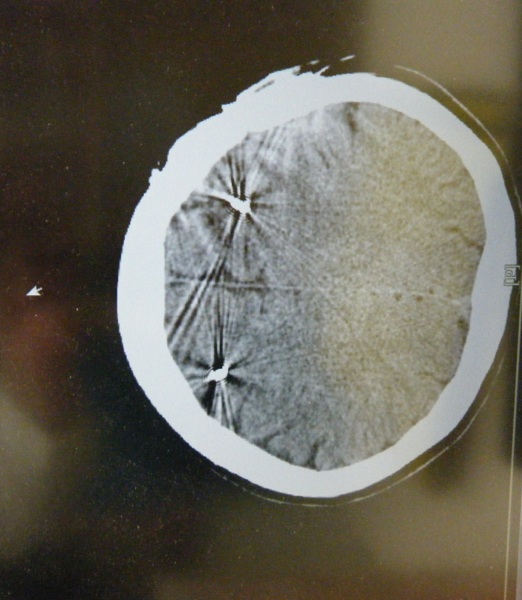

(患者的斷層掃描CT)

當患者到達急診室後,家屬跟急診室醫生告知病史時,提到了DBS,當下兩位

值班醫師都對此手術沒有印象,只好送患者去照X-RAY,我也想知道到底是什麼手

術,到底蟑螂的鬚鬚是啥?結果在X光及CT後一覽無遺,原來是這樣的一個手術,利

用調節器經過導線來調節大腦的電流(簡單來說應該是這樣).這種手術或許不常見,

DBS手術包括了植入一個細長的電極導線(electrode),至腦中的丘腦下核(subthalamus nucleus,STN)或是蒼白球內核(globus pallidus internal segment,GPi),此一導線經皮下和植入於胸前的脈衝產生器(pulse generator)相連(此一裝置,類似於心律調節器)。不同於燒灼手術,DBS不會破壞腦部組織,它是一種可逆式的反應,藉著產生電流來控制調節腦內不正常的活動訊息,而達到運動症狀的控制。目前DBS已成為治療巴金森氏病最有效的手術方式,但它也是非常複雜及精細的一種手術。此外,在達到它的效果之前,病人必須經過一段調適期及有耐心的等待。